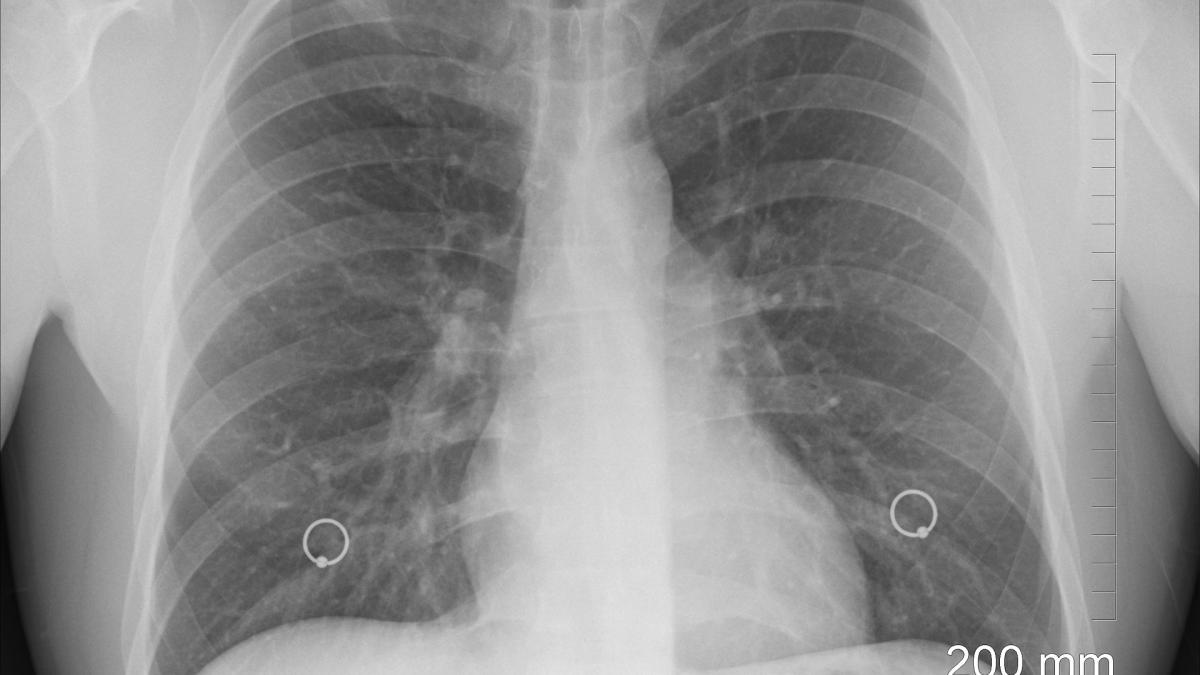

Comitetul Național de Coordonare a Activităților privind Vaccinarea a publicat o imagine în care arată cum afectează COVID-19 plămânii umani.

Comitetul Național de Coordonare a Activităților privind Vaccinarea (CNCAV) a publicat o imagine comparativă între un plămân sănătos și unul afectat de coronavirus. După cum se poate observa în imagine, virusul SARS-CoV-2 a afectat aproape în totalitate plămânii.

„Plămân afectat de COVID-19 versus plămân sănătos

În imaginea din partea stângă este radiografia pulmonară a unui tânăr, în vârstă de 23 ani, cu o saturație de 72%.

Tânărul infectat, nevaccinat

Tânărul s-a infectat la mare și, din păcate, nu este vaccinat împotriva COVID-19.

În imaginea din partea dreaptă este o radiografie normală a unei persoane sănătoase. Diferențele sunt vizibile, chiar dacă o saturație normală presupune peste 95%.